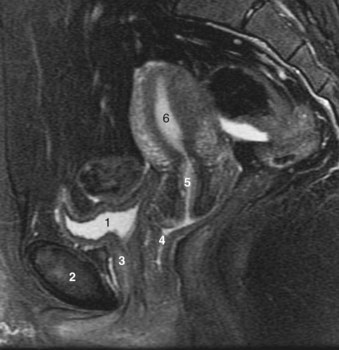

The rectum begins with the disappearance of the sigmoid mesentery opposite the third sacral vertebra. Peritoneum continues anteriorly over the upper two thirds of the rectum as the rectovesical pouch in males and as the rectouterine pouch (of Douglas) in females (Fig. 2–27; see also Fig. 2–11). Incision of the anterior wall of this peritoneal pouch exposes the seminal vesicles behind the bladder. Inferior to this pouch, the anterior rectum is related to its fascial continuation (the rectogenital or Denonvilliers fascia) down to the level of the striated urethral sphincter (see Figs. 2-4, 2-27, and 2-28). The rectum describes a gentle curve on the sacrum, coccyx, and levator plate (see Fig. 2–24) and receives innervation from the laterally placed pelvic autonomic plexus and blood supply from the superior (from inferior mesenteric), middle (from internal iliac), and inferior (from internal pudendal) rectal arteries.

Figure 2–27 Sagittal section through the prostatic and membranous urethra, demonstrating the midline relations of the pelvic structures.

The normal prostate weighs 18 g; measures 3 cm in length, 4 cm in width, and 2 cm in depth; and is traversed by the prostatic urethra (see Fig. 2–27). Although ovoid, the prostate is referred to as having anterior, posterior, and lateral surfaces, with a narrowed apex inferiorly and a broad base superiorly that is contiguous with the base of the bladder. It is enclosed by a capsule composed of collagen, elastin, and abundant smooth muscle. Posteriorly and laterally, this capsule has an average thickness of 0.5 mm, although it may be partially transgressed by normal glands. Microscopic bands of smooth muscle extend from the posterior surface of the capsule to fuse with Denonvilliers fascia. Loose areolar tissue defines a thin plane between Denonvilliers fascia and the rectum. On the anterior and anterolateral surfaces of the prostate, the capsule blends with the visceral continuation of endopelvic fascia. Toward the apex, the puboprostatic ligaments extend anteriorly to fix the prostate to the pubic bone. The superficial branch of the dorsal vein lies outside this fascia in the retropubic fat and pierces it to drain into the dorsal vein complex.

The urethra runs the length of the prostate and is usually closest to its anterior surface. It is lined by transitional epithelium, which may extend into the prostatic ducts. The urothelium is surrounded by an inner longitudinal and an outer circular layer of smooth muscle. A urethral crest projects inward from the posterior midline, runs the length of the prostatic urethra, and disappears at the striated sphincter (Fig. 2–35). To either side of this crest, a groove is formed (prostatic sinuses) into which all glandular elements drain (McNeal, 1972). At its midpoint, the urethra turns approximately 35 degrees anteriorly, but this angulation can vary from 0 to 90 degrees (see Figs. 2-27, 2-31, 2-36, and 2-37). This angle divides the prostatic urethra into proximal (preprostatic) and distal (prostatic) segments that are functionally and anatomically discrete (McNeal, 1972, 1988). In the proximal segment, the circular smooth muscle is thickened to form the involuntary internal urethral (preprostatic) sphincter described earlier. Small periurethral glands, lacking periglandular smooth muscle, extend between the fibers of the longitudinal smooth muscle to be enclosed by the preprostatic sphincter. Although these glands constitute less than 1% of the secretory elements of the prostate, they can contribute significantly to prostatic volume in older men as one of the sites of origin of benign prostatic hypertrophy.

Figure 2–37 Retrograde urethrogram of the male urethra demonstrating urethral anatomy. 1, prostatic urethra; 2, verumontanum, into which enter the ejaculatory ducts; 3, membranous urethra, note physiologic narrowing of urethral luminal diameter due to external striated sphincter; 4, bulbar urethra; 5, pendulous urethra.

Beyond to the urethral angle, all major glandular elements of the prostate open into the prostatic urethra. The urethral crest widens and protrudes from the posterior wall as the verumontanum (see Figs. 2-35, 2-37, and 2-38). The small slitlike orifice of the prostatic utricle is found at the apex of the verumontanum and may be visualized cystoscopically. The utricle is a 6-mm müllerian remnant in the form of a small sac that projects upward and backward into the substance of the prostate. In males with ambiguous genitalia, it may form a large diverticulum that protrudes from the posterior side of the prostate. To either side of the utricular orifice, the two small openings of the ejaculatory ducts may be found. The ejaculatory ducts form at the juncture of the vas deferens and seminal vesicles and enter the prostate base, where it fuses with the bladder. They course nearly 2 cm through the prostate in line with the distal prostatic urethra and are surrounded by circular smooth muscle (see Fig. 2–36; see also Figs. 2-27 and 2-31).